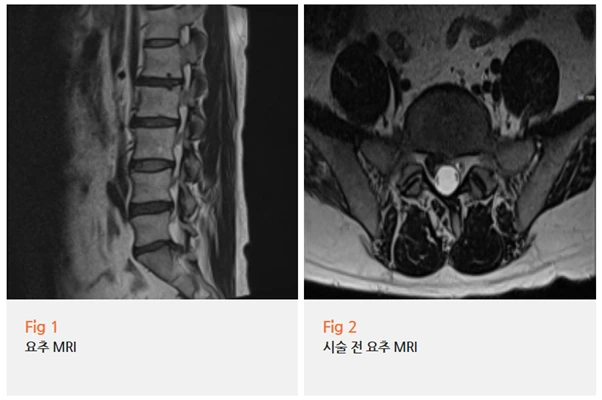

%EA%B7%B8%EB%A6%BC3.png?type=w966

다음 날 환자분께서 연락을 주셨어요.

다리저림이 훨씬 줄었다고요.

그리고 4개월 후, 재촬영한 MRI에서 신경 협착이 확연히 감소된 것을 영상으로 직접 확인했습니다.